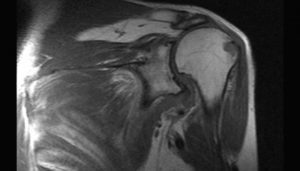

Результатом МР-сканирования являются послойные изображения исследуемой области в трех, взаимноперпендикулярных проекциях. Анализом фото занимается врач-рентгенолог, который фиксирует и описывает любые отклонения структуры сустава от нормы.

На снимках преобладают серые оттенки, интенсивность которых зависит от плотности обследуемых структур. При необходимости на экране монитора создается трехмерное изображение, наиболее информативное при проведении МРТ с контрастным веществом.

Интерпретацией полученных результатов занимается врач лучевой диагностики. Расшифровка обычно не занимает больше 2 часов, однако при загруженности рентгенолога пациентам приходится ждать результатов в течение суток. Что показывает МРТ плечевого сустава:

Во время расшифровки результатов оценивается состояние костных поверхностей, выстланных хрящевыми тканями. В норме на них не должно быть выраженных дефектов. Исследуются и расположенные рядом с сочленением связки, сухожилия, нервные пучки, мышечные волокна. Изменения мягкотканных структур часто указывают на вялотекущий воспалительный процесс.